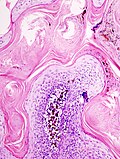

|

Seborrheic keratosis. H&E stain. | |

| LM | horn cysts, pigmented basal layer, hyperkeratosis |

Features:[2]

- Raised above skin surface.

- Border sharply demarcated.

- Hyperkeratosis - stratum corneum extra thick.

- Horn cysts - intraepidermal collections of keratin - key feature.

- Clusters of cells with brown granular material in the superficial dermis/dermoepidermal junction - pigmented melanocytes.